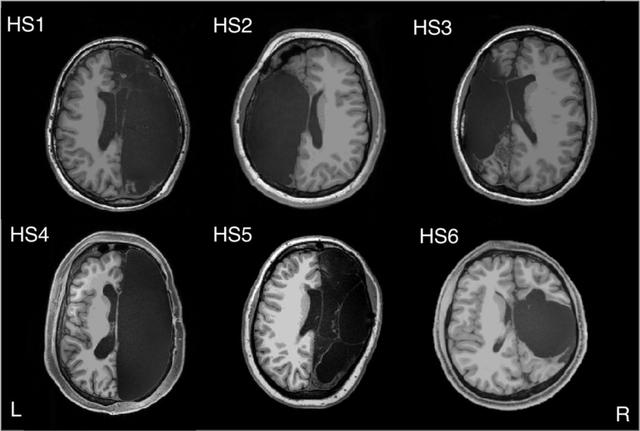

近日,美國(guó)加州理工學(xué)院的研究人員對(duì) 6 名只有半個(gè)大腦的成年人進(jìn)行了深入研究。這 6 名研究對(duì)象在童年時(shí)期因癲癇治療而切除了一側(cè)大腦半球,通過(guò)對(duì)這些看似正常人的患者進(jìn)行腦部磁共振(MRI)掃描成像,結(jié)果發(fā)現(xiàn)切除了半個(gè)大腦的患者之所以能夠維持正常的生活能力,是因?yàn)檫@些人的大腦剩余部分能夠進(jìn)行自適應(yīng)調(diào)整,在不同功能的神經(jīng)網(wǎng)絡(luò)之間形成了異常強(qiáng)烈的神經(jīng)連接。

圖 | 大腦半球切除術(shù)患者 MRI 掃描圖像(來(lái)源:Caltech Brain Imaging Center)

圖 | 6 名接受過(guò)大腦半球切除術(shù)的患者大腦 MRI 圖像(來(lái)源:Cell Reports)